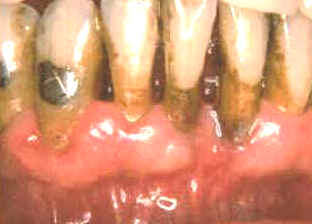

Estas imágenes muestran inmediatamente como queda luego de la limpieza con instrumental  ultrasónico. La gingiva se desprende del diente y la mayoría del epitelio de la bolsa periodontal queda expuesto. El  sangrado durante el tratamiento es intenso y el paciente suele notar algún sangrado post operatorio de la encía. Los tejidos blandos suelen molestar.

Durante algunos días el paciente al comer y cepillar sus dientes, puede presentar síntomas de dolor y sangrado. Suele ocurrir  bacteremia  durante el tratamiento y durante algunos días posteriores debido al cepillado dental. El tejido conjuntivo expuesto y el epitelio frágil permiten el pasaje de las bacterias orales a los vasos sanguíneos. Deben administrarse antibióticos  en forma profiláctica  en los  pacientes  que presentan condiciones sistémicas riesgosas si ocurriera una bacteremia.